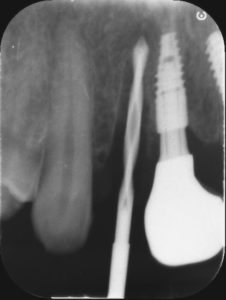

こちらは部分的なレントゲン写真です。

この様にインプラントを入れる位置を確認しながら行っていきます。